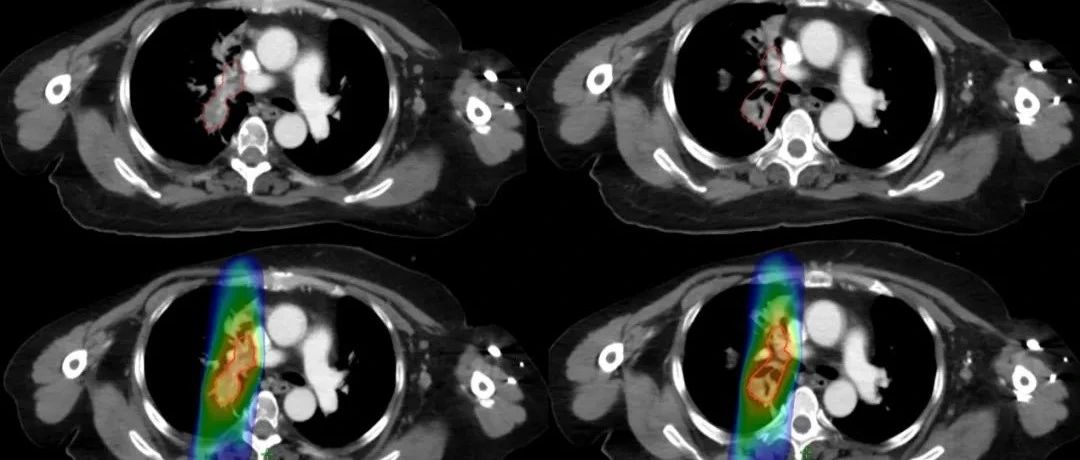

【學科風采】乳腺癌患者千里求醫(yī),成功治療多發(fā)腦轉移瘤、脊髓轉移、腦膜轉移、椎管內多發(fā)轉移結節(jié)、肺炎及肺門轉移患者